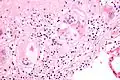

Micrograph of asteroid bodies in pulmonary sarcoidosis. H&E stain. -